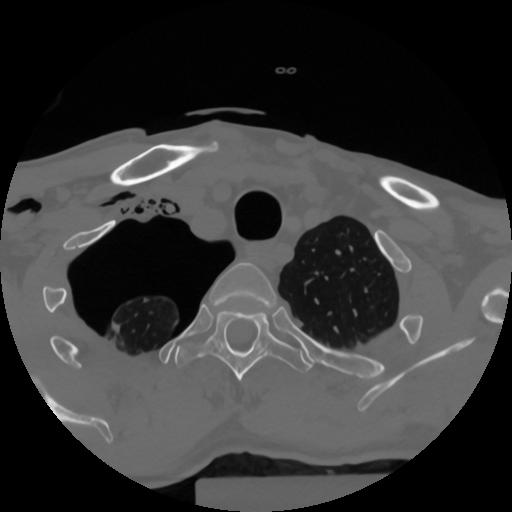

12 P.BLANDAS,,Vol,0.5,P.BLANDAS,,